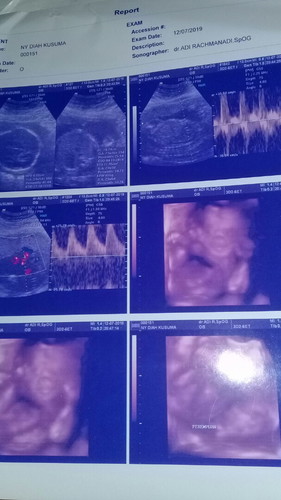

Pas USG hr jum'at kemaren udah 24 minggu.alhamdulillah kata dokter semua normal n sehat..cuma di suruh ngurangin yg manis"padahl paling suka sama yg manis"...sola nya takut yg nambh bb ibu nya ..nanti susah buat lahiran...emang ngaruh ya bunda"...